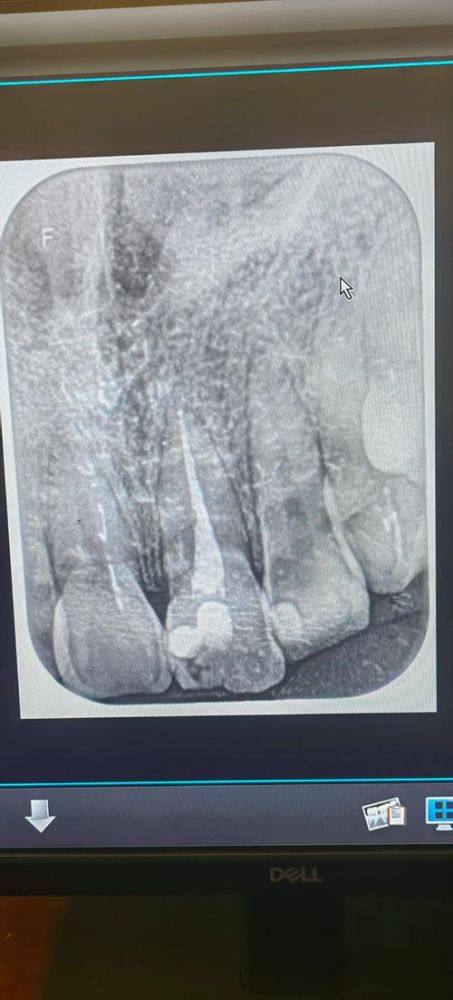

牙髓病诊疗:能够精细判断各类牙髓病症,采用合适的治疗方案,缓解患者牙齿疼痛等不适,修复牙齿正常功能。